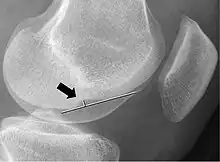

Deep lateral femoral notch sign

Measurement technique to determine the depth of the femoral notch on lateral x-rays